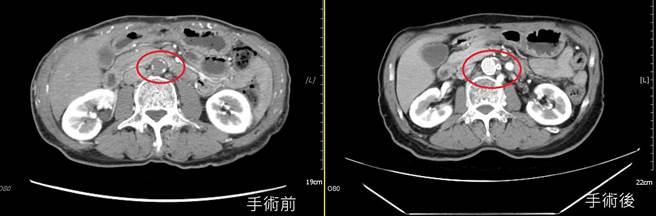

亚洲大学附属医院心臟外科主任刘殷佐透过触诊检查双侧股动脉,发现患者脉搏微弱,足背及胫后动脉察觉不出脉动,疑是血管阻塞,经电脑断层检查,患者肚脐上8公分处以下的主动脉及双侧总肠骨动脉完全阻塞,且双侧外肠骨动脉狭窄。

刘殷佐指出,影像检查显示,患者的腹主动脉、髂骨动脉以及上肠繫膜动脉等,都有阻塞情形,确认为「髂主动脉血管阻塞症候群」(Leriche Syndrome),此病主要特徵会以跛行、双下肢脉搏下降、勃起困难表现,因此也俗称「脚中风」。

刘殷佐表示,与患者讨论后替其安排导管手术置放支架,先从患者的鼠蹊部及手臂动脉置放导管,接着在血管腔打通腹主动脉阻塞部位,最后将5支支架置放在右髂动脉,一举改善阻塞问题;患者术后5小时即可下床走动,术后第5天即康復返家,患者回诊时还透露,术后一併改善勃起困难,相当感谢。